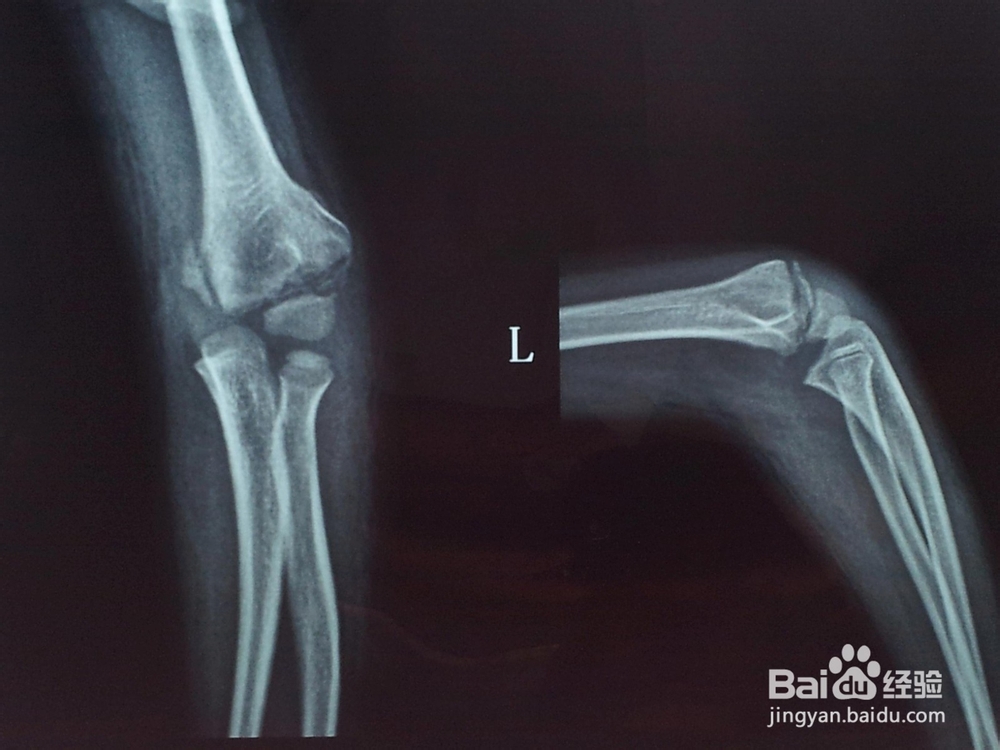

2、骨骺线检查:身高增长的原理是骨骼的增长,不再增长的原因是骨骺线的闭合。通过区医院做一个骨骺线的X光平扫,可以很轻松地了解自己的骨骺线是否闭合。如果还未闭合,那么身高依然有增长的希望,反之则不会长高了。